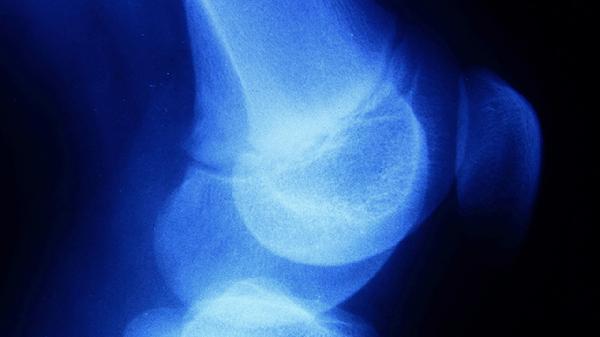

骨膜炎患者可遵医嘱使用布洛芬缓释胶囊、塞来昔布胶囊、硫酸氨基葡萄糖胶囊、双氯芬酸钠缓释片、洛索洛芬钠片等药物缓解症状。骨膜炎可能与外伤、慢性劳损、感染等因素有关,通常表现为局部红肿、压痛、活动受限等症状。

硫酸氨基葡萄糖胶囊可促进软骨基质修复,改善关节功能,适用于慢性骨膜炎伴软骨损伤者。需连续服用较长时间才能显效,少数患者可能出现轻度胃肠反应。